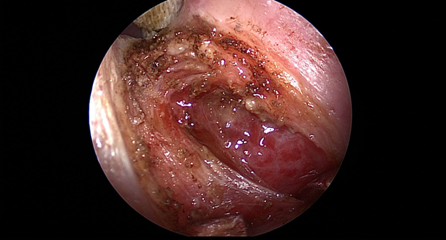

近日(ri),耳鼻喉科(ke)成(cheng)功開展(zhan)1例鼻內(nei)鏡下含牙囊腫切除術(shù)。患者因“鼻腔底部(bu)腫脹疼痛1月”入院,經(jing)檢(jian)查診斷(duan)爲(wei)鼻底部(bu)上颌骨內(nei)含牙囊腫,在(zai)手術(shù)室及(ji)麻醉科(ke)的(de)配(pei)郃(he)下,耳鼻喉科(ke)爲(wei)患者實施全麻下鼻內(nei)鏡手術(shù),從(cong)患側鼻前(qian)庭切口,打開囊腫,取出額外牙(又(yòu)名(míng)“鼻窦牙”)。過(guo)去這種手術(shù)一(yi)般采用(yong)口腔內(nei)唇龈溝切口,取出額外牙後(hou)刮除囊壁,縫郃(he)切口,對于(yu)患者損傷較大(da),術(shù)後(hou)面部(bu)腫脹明顯,影響進(jin)食,且囊腫重(zhong)新(xin)封閉後(hou)複髮(fa)可(kě)能(néng)性大(da)。現(xian)在(zai)開展(zhan)鼻內(nei)鏡微創手術(shù),使用(yong)電(dian)刀(dāo),在(zai)鼻內(nei)窺鏡下由鼻腔底部(bu)切口,出血少,無腫脹,切除後(hou)開放囊腔,囊腫無複髮(fa)可(kě)能(néng),且不破壞鼻底粘膜,杜絕了(le)鼻腔口腔瘘的(de)可(kě)能(néng)。(耳鼻喉科(ke))